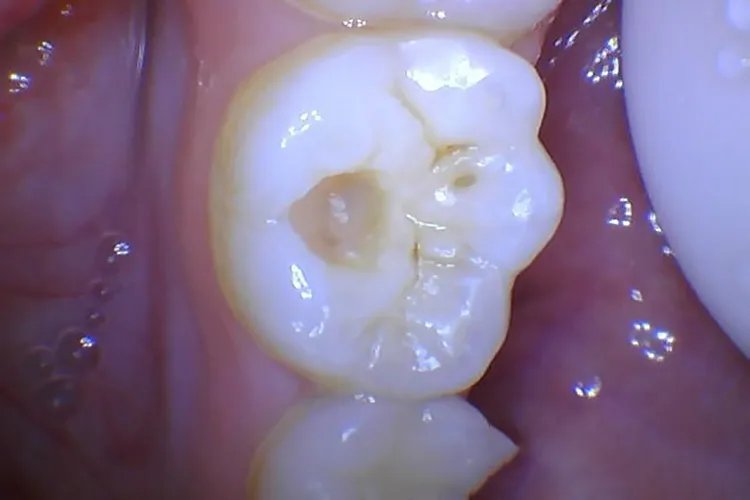

中龋中龋龋损部位表现为牙本质呈黄褐色或深褐色,龋洞形成,牙体缺损明显,病变牙本质质地较软。患者对酸、甜刺激敏感,过冷、过热饮食也能产生酸痛感觉,冷刺激尤为显著,刺激去除后症状立即消失。